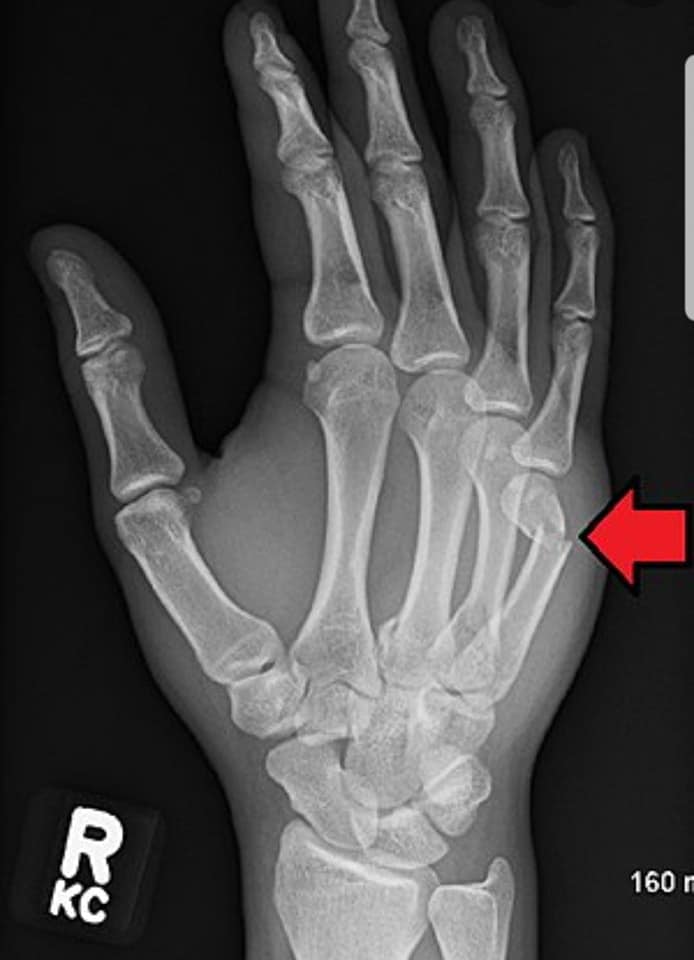

Гэмтэл согог судлалын үндэсний төвийн Гар сарвуу нөхөн сэргээх бичил мэс заслын тасгийн эрхлэгч Л.Нанжид: - Сээрний ясыг гараараа цохих нь шууд утгаараа, ясыг ясаар цохиж байгаа хэрэг. Мэдээж аль…